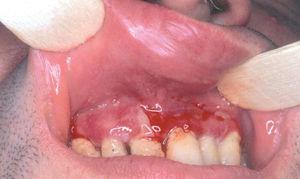

Un varón de 41 años fue remitido por su dentista con el diagnóstico de liquen de mucosa oral, desde hacía un año. Las lesiones le estaban produciendo molestias progresivas, con dificultad para comer y tragar. La aplicación de corticoides no produjo mejoría clínica de las lesiones. La exploración física reveló la presencia de eritema en encía superior e inferior con zonas erosivas (fig. 2). Además, en mucosa yugal se observaban también zonas erosivas. En el margen interno de mucosa conjuntival presentaba inyección leve, con áreas de fibrosis y sinequias incipientes (estadio II de Foster 9) (fig. 3). La exploración de la mucosa faríngea reveló eritema y erosiones en esta localización. Los hallazgos clínicos y los estudios llevados a cabo 8 permitieron diagnosticar al paciente de PM, con afectación oral y ocular (tabla 1). La administración de prednisona al 0,5 mg/kg/día no resultó eficaz, y por este motivo se inició tratamiento con cuatro sesiones de plasmaféresis, al final de las cuales se inició tratamiento con bolo de ciclofosfamida (750-1.000 mg/m 2), que se repitieron mensualmente hasta un total de cinco. Este tratamiento se complementó con dapsona (100 mg/día) junto a vitamina E, 800 mg/día, pero que tuvo que suspenderse por colestasis medicamentosa. La mejoría del paciente fue progresiva, el eritema y las úlceras desaparecieron, por lo que se fue disminuyendo progresivamente la administración de prednisona hasta suspenderla. El paciente presenta únicamente lesiones ulcerosas aisladas ocasionales, en las que se aplica dipropionato de betametasona al 0,05 %, con lo que se resolvieron en pocos días. No ha vuelto a presentar molestias oculares ni faríngeas.

Fig. 2.--Eritema y erosiones, con ampollas rotas localizadas en la mucosa gingiva inferior (paciente 2).